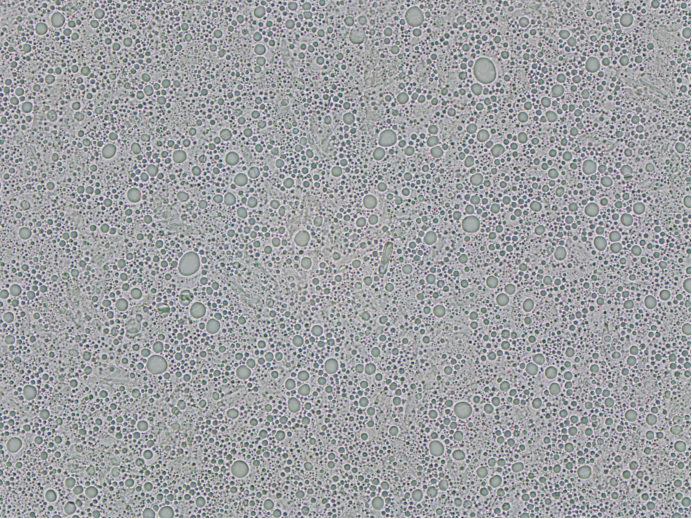

梓夢(mèng)科技顯微鏡法粒度分析儀ZML310則采用高分辨率光學(xué)成像技術(shù),能夠直接捕捉到顆粒的清晰微觀圖像。操作人員通過(guò)儀器配備的2000萬(wàn)像素高清相機(jī),可直觀觀察到顆粒的大小、形狀、表面顏色等細(xì)節(jié)特征,無(wú)論是球形、異形,還是粘連、團(tuán)聚的顆粒,都能清晰呈現(xiàn)。同時(shí),結(jié)合專業(yè)的顯微圖像分析軟件,儀器可對(duì)顆粒的粒度進(jìn)行精準(zhǔn)測(cè)量,包括粒徑、粒徑分布、等效直徑等多項(xiàng)參數(shù)。這種 “直觀觀察 + 精準(zhǔn)測(cè)量” 的模式,實(shí)現(xiàn)了粒度與形態(tài)的雙重檢測(cè),避免了激光粒度儀因無(wú)法識(shí)別形態(tài)而產(chǎn)生的誤判。在醫(yī)藥行業(yè)的粒度檢測(cè)中,梓夢(mèng)科技顯微鏡法粒度分析儀ZML310能清晰分辨出不同形態(tài)的顆粒狀態(tài),準(zhǔn)確測(cè)量其粒度,可清晰展示各類形態(tài)顆粒的占比情況,為優(yōu)化制劑工藝提供更全面、可靠的依據(jù)。

另一方面,針對(duì)不均勻混合樣品,梓夢(mèng)科技顯微鏡法粒度分析儀可通過(guò)多點(diǎn)取樣、統(tǒng)計(jì)分析的方式,全面掌握樣品的粒度分布情況。例如在混懸液樣品中,可通過(guò)在不同區(qū)域選取多個(gè)觀察點(diǎn),分別統(tǒng)計(jì)各點(diǎn)的顆粒數(shù)量及粒徑大小,再通過(guò)軟件系統(tǒng)對(duì)所有數(shù)據(jù)進(jìn)行整合分析,最終得到能夠真實(shí)反映整體樣品粒度特征的分布結(jié)果,有效避免了因樣品局部不均導(dǎo)致的檢測(cè)偏差,解決了激光粒度儀在檢測(cè)此類樣品時(shí)易出現(xiàn)的“以偏概全”問(wèn)題。